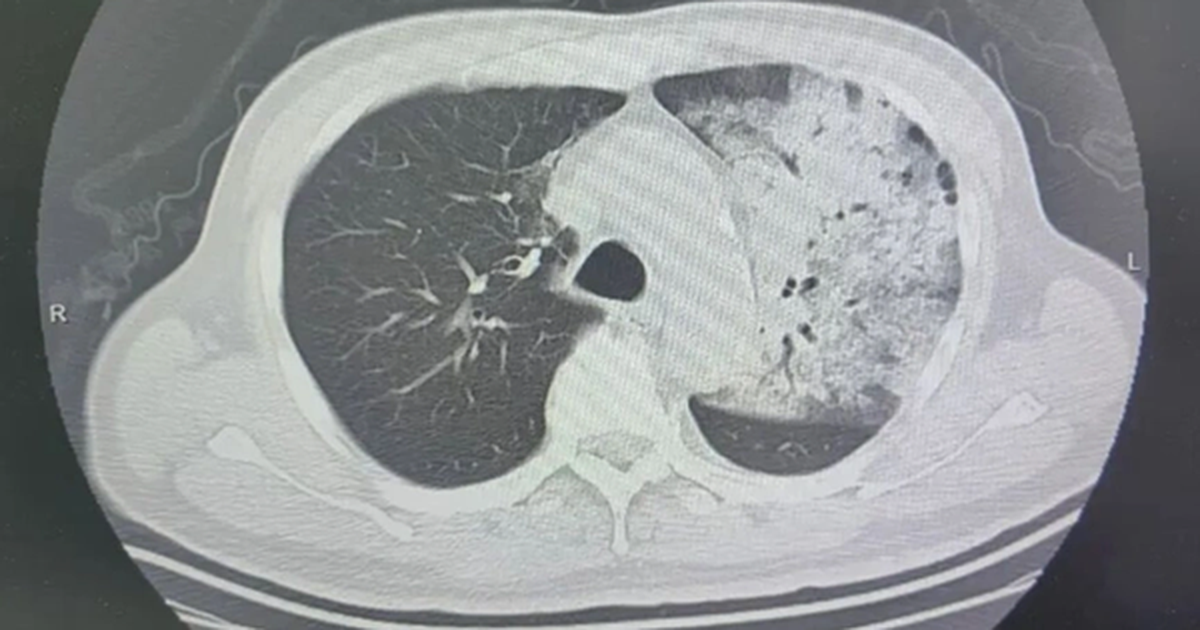

Các bác sĩ cho biết, cách duy nhất để kéo dài sự sống cho Chi là ghép tim. Khi nghe tin con gái có cơ hội được “thay tim”, bố mẹ em vừa mừng vừa lo. Mừng vì cánh cửa hy vọng đã mở ra nhưng nỗi lo cũng chồng chất: Tiền đâu để thực hiện ca ghép. Gia đình chạy vạy khắp nơi, gom góp được một phần chi phí nhờ sự hỗ trợ của các nhà hảo tâm. Nhưng một nỗi trăn trở khác lại day dứt: Tim đâu để ghép?

Các chỉ số của bé Chi khi ấy mới 10 tuổi phù hợp với trái tim hiến tặng. Ngày 1/10/2019, ca ghép tim được tiến hành tại Bệnh viện Hữu nghị Việt Đức (Hà Nội) và đã thành công.